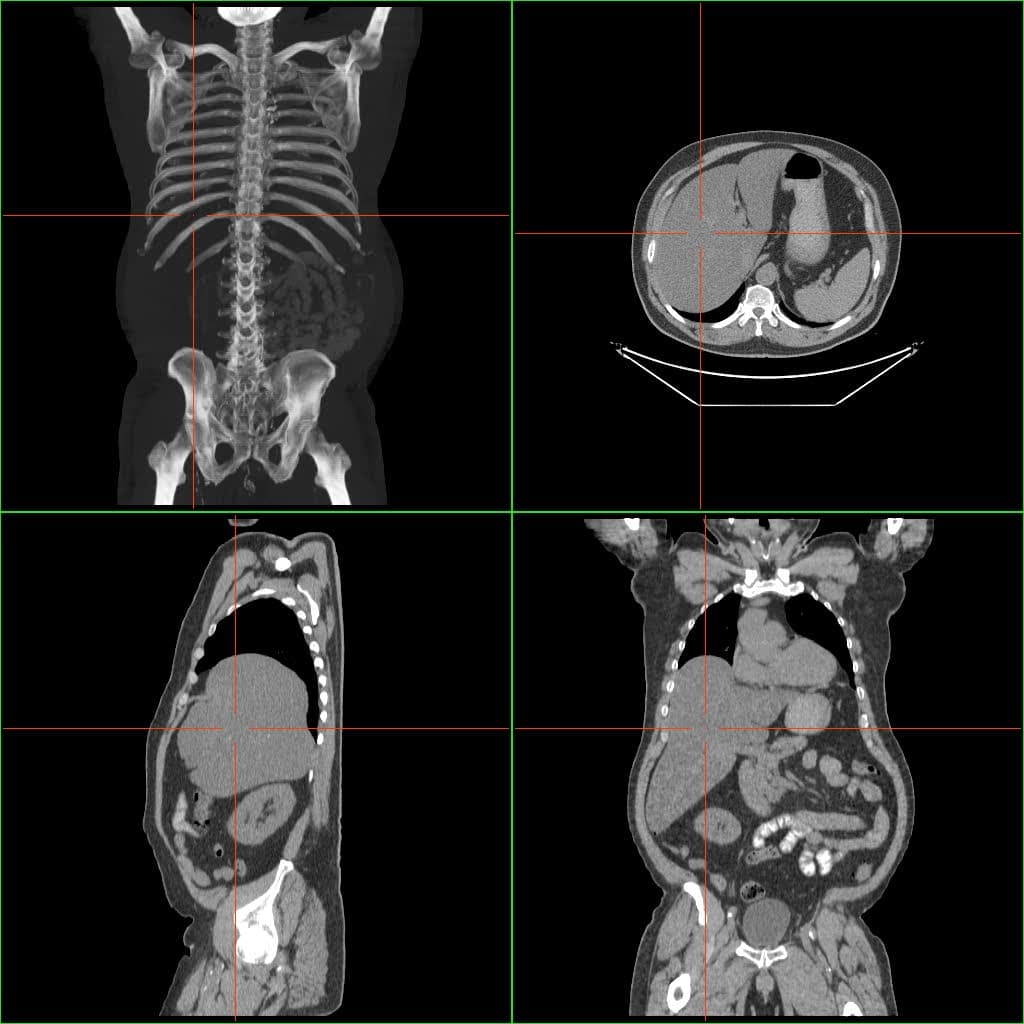

Hepatomegali atau adalah pembesaran ukuran hati sehingga bisa teraba dari luar pada pemeriksaan fisis abdomen. Hepatomegali bukanlah penyakit, tetapi merupakan tanda ada masalah baik itu masalah intrahepatik maupun ekstrahepatik. Hepatomegali bisa menyebabkan keluhan berupa perut membesar, nyeri di perut kanan atas, atau penyakit kuning.[1][2][3]

Penyebab pembesaran hati antara lain karena penyebaran kanker, alkoholisme, gangguan pembuluh darah jantung, kanker hati, sirosis, virus, penyakit hati. kelainan yang menyebabkan protein abnormal tertimbun di hati seperti amiloidosis, gangguan genetik yang menyebabkan tembaga tertimbun di hati (penyakit Wilson), penyakit penimbunan besi di hati (hemakromatosis), penyakit penimbunan substansi lemak di hati (penyakit Gaucher), kista hati, tumor jinak, obstruksi kandung empedu, hepatitis toksik, gagal jantung dan blokade pembuluh darah vena yang memperdarahi hati (sindrom Budd-Chiari).[2][3][4]